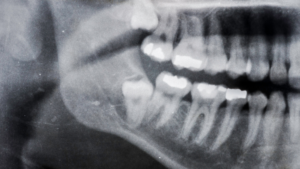

Crowding or Shifting of Nearby Teeth

Wisdom teeth can push against neighboring teeth as they attempt to emerge, leading to crowding or shifting in the dental arch. This movement can affect alignment and may undo previous orthodontic work. Changes in how teeth fit together may be subtle at first but become more noticeable over time. Monitoring these changes is important.

Additionally, crowding can create tight spaces that are difficult to clean, increasing the risk of cavities and gum disease. Addressing the issue early helps preserve alignment and overall oral health. Preventing these changes can reduce the need for additional treatment. Early intervention supports better outcomes.